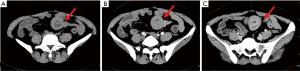

Case 3 was a 27-year-old man who presented with a 5-year history of intermittent and progressive abdominal pain and melena. Capsule endoscopy 5 years prior had revealed small intestine polyps with multiple venous malformations; however, all symptoms improved with pharmacological management. The patient was later admitted to hospital with recurrent abdominal cramping. Physical examination was unremarkable, and laboratory data were negative; however, fecal occult blood was positive, and CT revealed an ileal intussusception (Figure 3). A 3 cm tubular structure with an abundant fatty component was found at the proximal end of the intussusception. Due to the presence of melena and an associated hemoglobin drop from 108 to 91 g/L in 3 days, the patient underwent emergency laparotomy where ileo-ileal intussusception was found approximately 140 cm from the ileocecal valve. A segmental ileal resection with ileoileostomy was performed. Histological examination was typical of HP tissue, and the patient was discharged 5 days later following an unremarkable postoperative course.